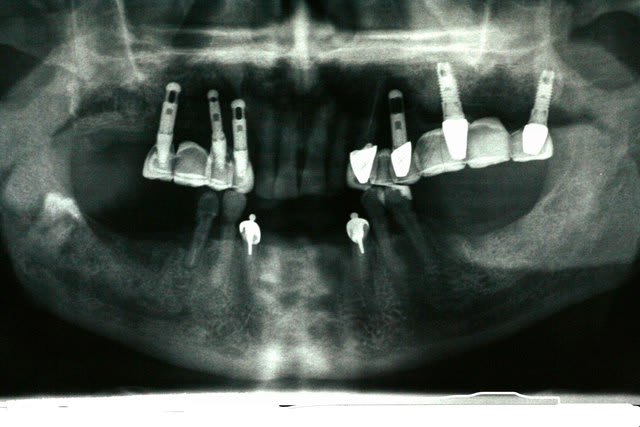

1er cas: une belle réussite chirurgicale et un massacre prothétique

2ème cas: une belle réussite prothétique(aucune mobilité, esthétiquement acceptable malgré la position des implants) et un massacre chirurgicale (6 ans)

C'est des implants zygomatiques sur ton premier cas ?

et 1 orbiculaire

désolé orbitaire

je n'ai rien fait au patient: il voulait un avis sur son état actuel

l'implant est bien sous l'orbite

inconscience ou non?